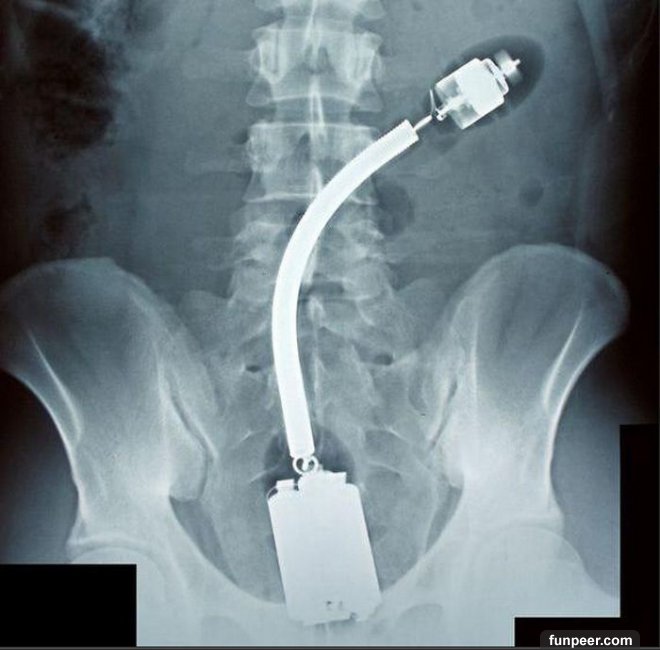

自慰惹禍,留在女人身體裏的自慰工具

單身的人性欲怎麼解決?有些人選擇了使用各種工具進行自慰。這一組X-Ray照射下的圖片,驚人地展示了人們使用的自慰工具品種之多,同時也提醒大家血淋淋的事實——胡亂使用自慰工具,是很容易出現事故的!就像這些X光片的患者一樣,要到醫院做手術取出。

有些人以為,到性用品店買個性工具總不會有危險了吧?錯!使用性用品也可能會出意外的。看看上面這兩個X光片,可憐的使用者居然把震動棒和假陰莖“安家”在體內了。所以提醒各位有意使用性工具的網友:1.購買性工具一定不能貪便宜,要購買品質信得過的;2.使用時要嚴格遵照使用說明,千萬不能隨心所欲;3.正規廠家的產品也難免會有某些出現意外,所以使用前要嚴格檢查它是否安全。

以上圖片這樣的自慰工具,真是令人大吃一驚。可美國有些所謂的“新潮”人,為了尋找刺激,想盡一切辦法尋找最“另類”的自慰工具。後果怎樣呢?看看X光片就知道了——得不償失!

【猜一猜】你能從這些X光片中看出他/她們使用的是什麼東西進行自慰嗎?